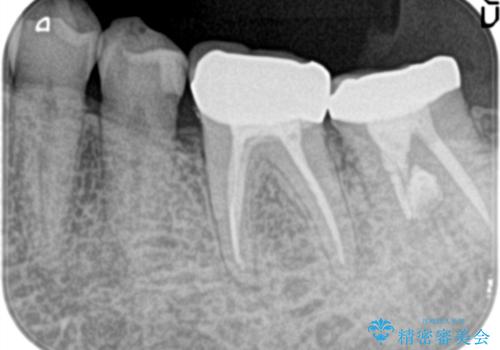

- 他院で治療したが、痛みが続いていることを主訴に来院されました。

痛みの原因歯を特定し、根管治療を行い、オールセラミッククラウンにて咬合回復しております。

根管治療は林先生に依頼しております。

根管治療後、精度の高い被せ物を入れることは歯の予後に大きく関わります。